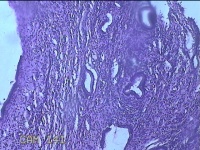

性别

女

年龄

28岁

临床诊断

子宫颈上皮瘤样病变

标本名称

宫颈9点组织

大体所见

灰白暗红色组织0.3x0.2x0.1cm两块。

图1